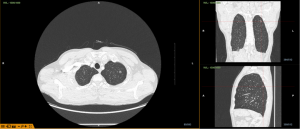

【一院技术】济宁市第一人民医院率先开展LungPro导航引导下气管镜染色定位肺结节精准切除术

随着低剂量CT扫描的普及,孤立性肺结节的检出率已提高到8%~...